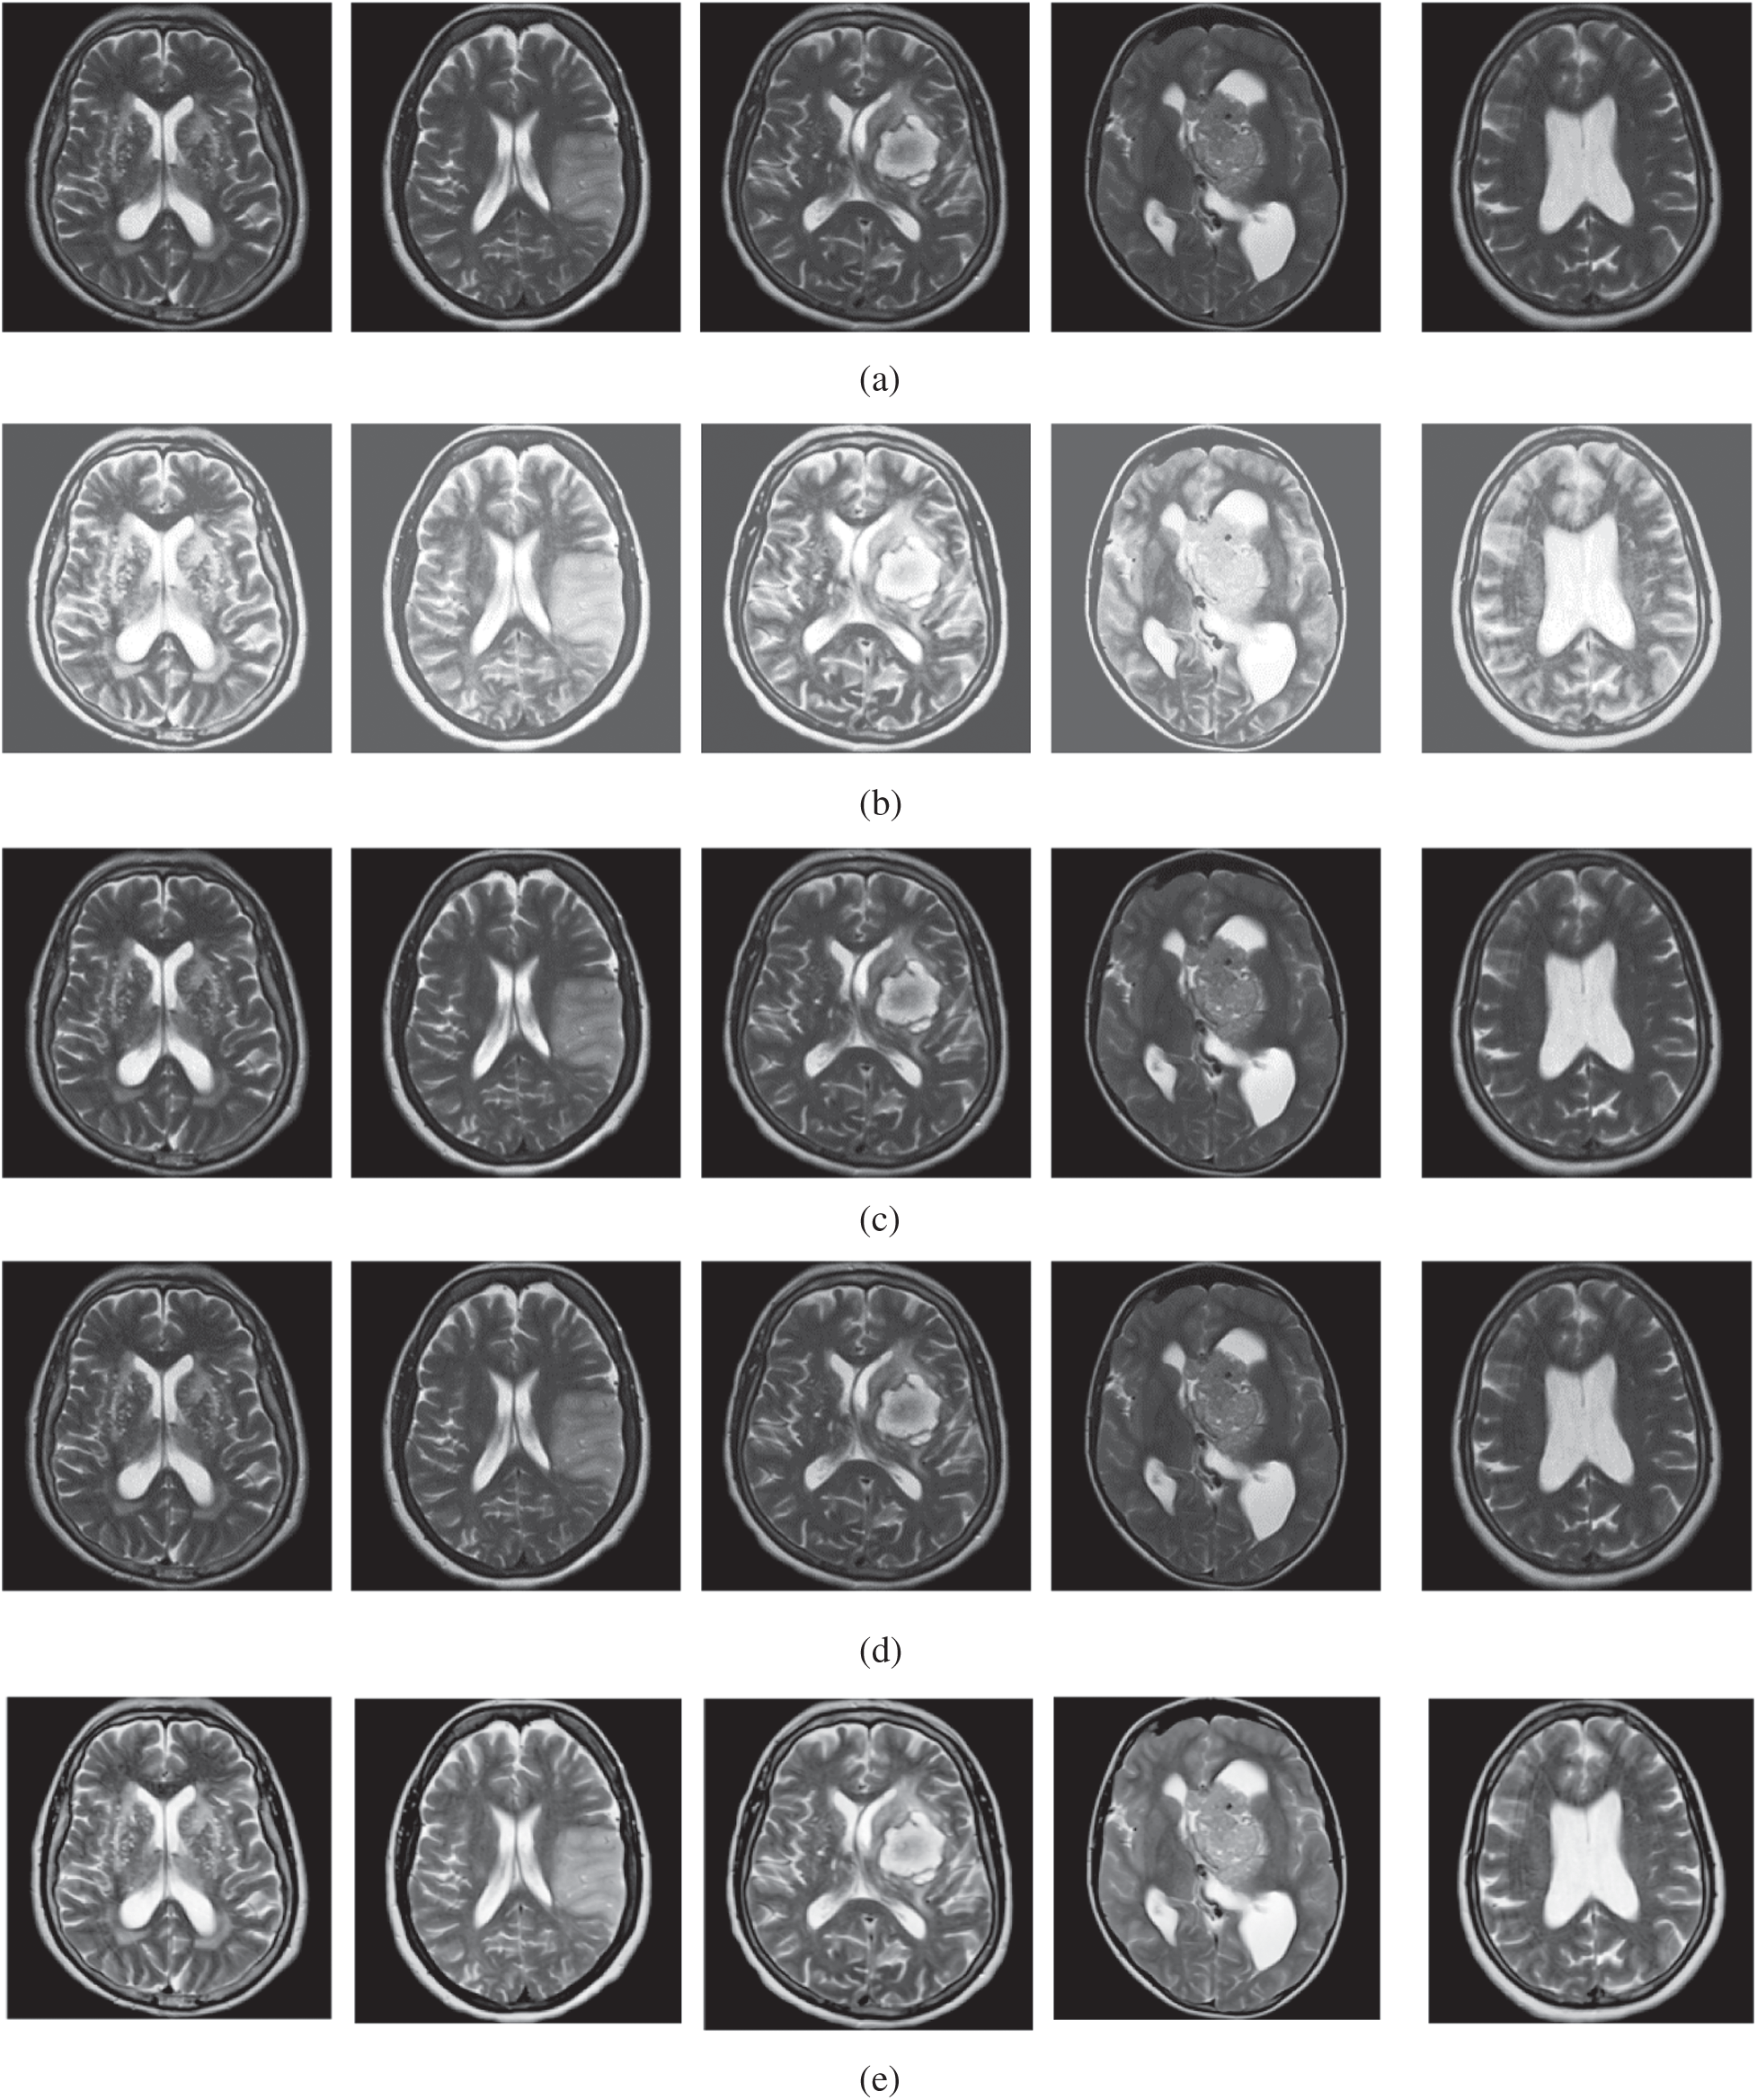

The qualitative results are illustrated in Fig. 3 for brain MRI; in Fig. 4 for lung CT, and in Fig. 5 for kidney MRI. As shown in the figures, all of the images have different trends with the dark and bright areas. It could be seen that the Histogram Equalization (b), Fu et al. [11] (f), and Zhang et al. [12] (h) methods produce over-enhanced images, while the proposed method produces natural appearance by enhancing the dark areas and maintaining the bright areas of input images. Overall, when we look at the input images and its enhanced images, the brightness of the fine details increases compared to the input images, irrespective of the content and application of the image. The brightening caused by the proposed FITE model makes the structures of the medical images well-defined and clear. The proposed FITE method introduces fair visual results for the weakly illuminated images. This is the contribution of fractional integral entropy in this study.

Figure 3: The brain MRI enhancement results of the proposed and existing enhancement models. (a) Input image, (b) histogram equalization, (c) Al-Shamasneh et al. [4], (d) Raghunandan et al. [7], (e) Al-Ameen et al. [10], (f) Fu et al. [11], (g) Li et al. [17], (h) Zhang et al. [12], (i) proposed FITE